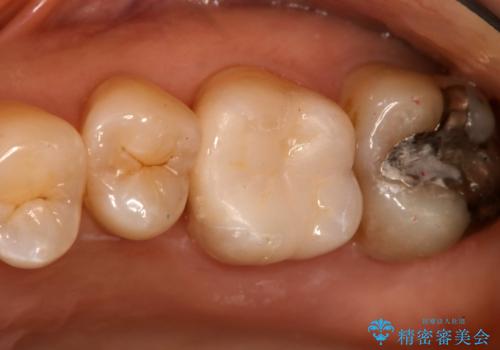

奥歯を白くしたい

- 左上6番の銀歯をセラミックにしたいと希望され来院された患者様です。

切削量を考慮し、セラミックインレーを選択しました。

銀歯を除去したところ虫歯が深かったので、CRを詰めた上で形態を整えています。